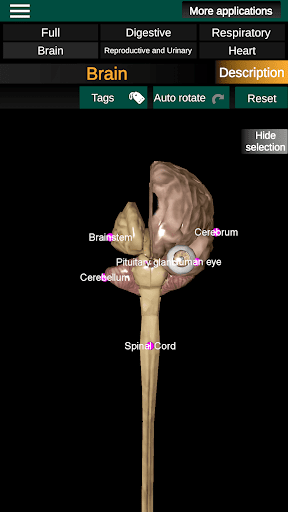

* Hersenen, waaronder de hersenen, het cerebellum en de hersenstam vallen.

* Gemakkelijk te openen en te navigeren (zoom, 3D-rotatie).

* Verberg of toon informatie.

* Beschrijvingen van elk orgel.